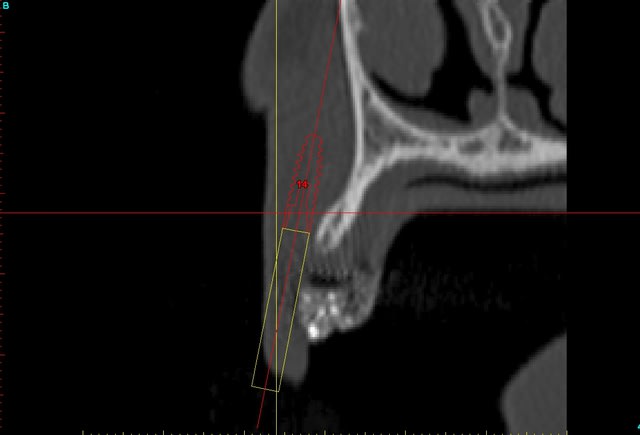

voilà, j'ai trouvé 5 mn...

le projet simplant est théorique, ça ne correspond pas à ce qui sera posé, c'était pour étude.